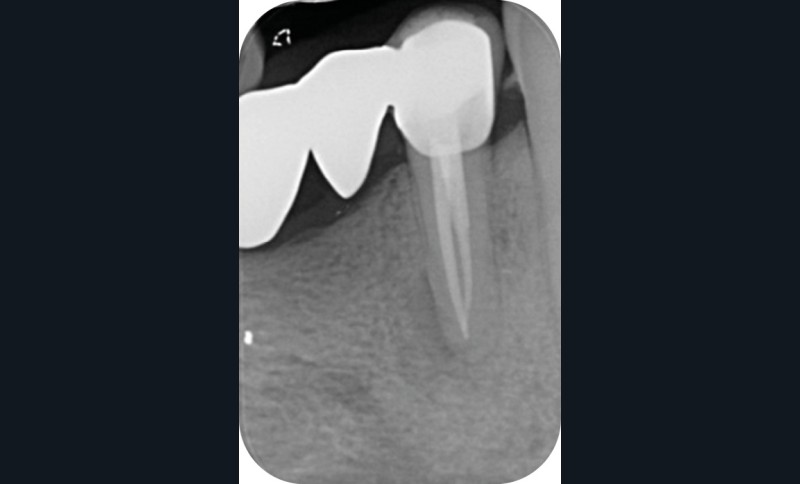

Une patiente de 56 ans, sans antécédents médico-chirurgicaux, se présente au Centre de soins dentaires pour cause de douleurs secteur 4. Les examens cliniques et radiographiques permettent d’orienter le diagnostic vers un abcès apical aigu sur la dent n°44 et de suspecter la présence d’un canal lingual non traité. Cette dent est support d’un bridge de grande étendue, de la dent n°44 à 47, étanche et apportant pleine satisfaction à la patiente (fig. 1).

La cavité d’accès endodontique était alors traditionnellement réalisée en se figurant les axes de la racine et du bridge (fig. 2). Cette aptitude à s’orienter dans l’espace n’est cependant pas aisée, et différents outils numériques offrent aujourd’hui la possibilité de dessiner la trajectoire suspectée du canal sur les coupes de l’examen Cone Beam et d’aider le praticien à planifier son futur geste thérapeutique (fig. 3, 4). Après pose du champ opératoire, une voie d’accès est ainsi réalisée à travers le bridge en reportant les mesures de la planification 3D (fig. 5). Le tenon est déposé par vibration avec un insert ultrasonore puis la lecture des teintes dentinaires sous microscope permet d’objectiver la présence d’un canal supplémentaire non traité (fig. 6). Les surplombs dentinaires sont supprimés avec un insert ET18D (Actéon) et les entrées canalaires relocalisées avec une lime rotative d’évasement coronaire.